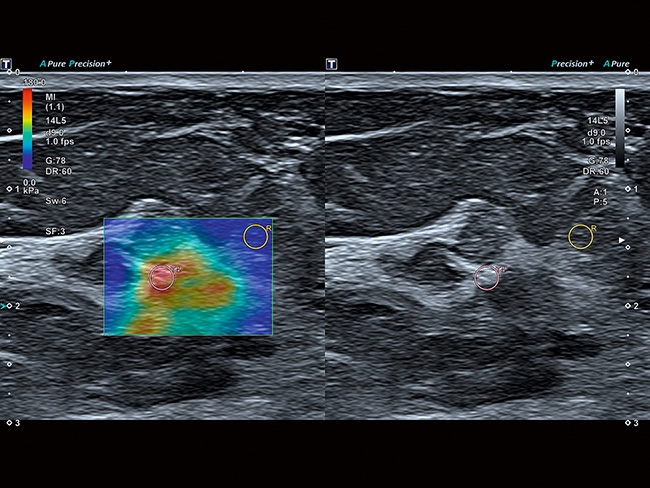

Aplio a550 может работать с линейным матричным датчиком и поддерживает новейшие монокристаллические датчики. Также Aplio a550 поддерживает большое количество дополнительных опций, таких как - SMI, Компрессионная эластография, Эластография сдвижной волны, Smart Fusion, исследования с использованием контраста (CEUS), 3D реконструкции в реальном времени (4D), функции автоматической оценки подвижности миокарда и фракции выброса.

• SMI. Опция, упрощающая визуализацию микроциркуляторного русла. С ее помощью обследуются сосуды с низкой интенсивностью кровотока, изучаются наиболее тонкие структуры. SMI упрощает диагностику новообразований, минимизирует вероятность ошибки.